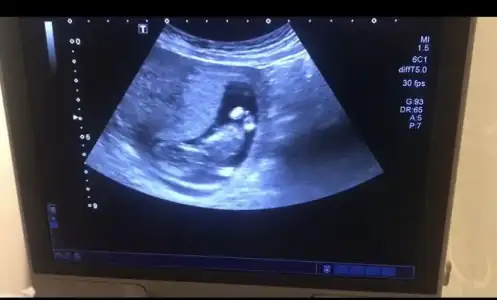

Doğru yere mi yazdım bilmiyorum ama benim bebeğime de bakar mısınız Kızlar 14 haftalık görüntü